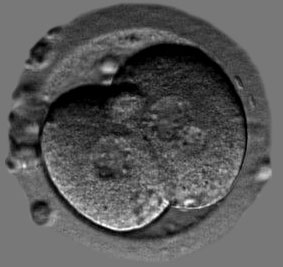

Fréquence des embryons multinucléés détectés par un système de time-lapse et son impact sur les issues de grossesses

L’évaluation de la qualité embryonnaire reste un élément primordial du choix des embryons à transférer. L’apparition de systèmes avec

time-lapse

permet l’évaluation de nouveaux critères de sélection tels que la multinucléation des blastomères et les temps de clivage.

Alors que la présence de blastomère(s) multinucléés au jour 2 de culture embryonnaire semble avoir un impact négatif sur les taux d’accouchement, qu’en est-il de la multinucléation au stade deux cellules ?